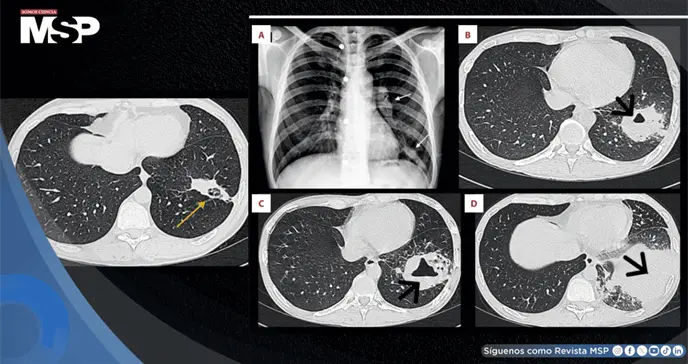

La radiografía de tórax mostró adenopatía hiliar izquierda y una opacidad mal definida en la zona inferior del pulmón izquierdo. Se solicitaron pruebas de VIH y estudios de bacilos acidorresistentes en esputo, pero no se realizaron ni recibieron seguimiento. Tampoco se tomaron hemocultivos.

La tomografía computarizada reveló una lesión cavitada de 55 por 41 milímetros en el lóbulo inferior izquierdo, acompañada de adenopatía hiliar izquierda y ganglios mediastínicos aumentados de tamaño.

Se programó una biopsia pulmonar que no se realizó por deficiencias en el seguimiento y coordinación. Tres semanas después, ante la persistencia de síntomas, se añadió levofloxacino. Sin embargo, a las siete semanas, una nueva tomografía mostró empeoramiento con una cavitación de 60 por 49 milímetros.

Aproximadamente cinco semanas después de iniciar la terapia antirretroviral, el paciente presentó nueva tos, fiebre y hemoptisis. La tomografía mostró empeoramiento con una consolidación cavitaria de 87 por 80 milímetros en el lóbulo inferior izquierdo, acompañada de nódulos, derrame pleural leve y adenopatías.